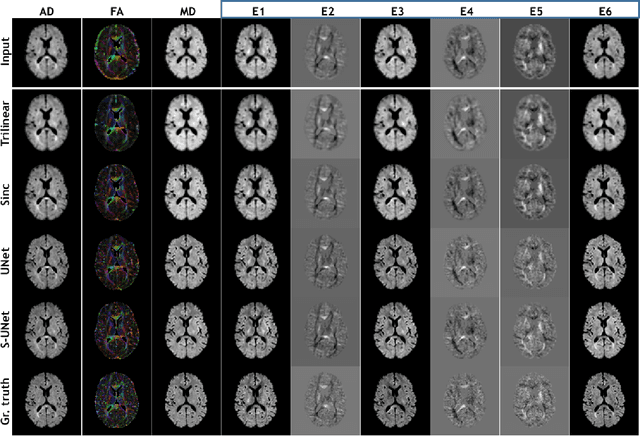

Abstract:Diffusion-weighted magnetic resonance imaging (DW-MRI) can be used to characterise the microstructure of the nervous tissue, e.g. to delineate brain white matter connections in a non-invasive manner via fibre tracking. Magnetic Resonance Imaging (MRI) in high spatial resolution would play an important role in visualising such fibre tracts in a superior manner. However, obtaining an image of such resolution comes at the expense of longer scan time. Longer scan time can be associated with the increase of motion artefacts, due to the patient's psychological and physical conditions. Single Image Super-Resolution (SISR), a technique aimed to obtain high-resolution (HR) details from one single low-resolution (LR) input image, achieved with Deep Learning, is the focus of this study. Compared to interpolation techniques or sparse-coding algorithms, deep learning extracts prior knowledge from big datasets and produces superior MRI images from the low-resolution counterparts. In this research, a deep learning based super-resolution technique is proposed and has been applied for DW-MRI. Images from the IXI dataset have been used as the ground-truth and were artificially downsampled to simulate the low-resolution images. The proposed method has shown statistically significant improvement over the baselines and achieved an SSIM of $0.913\pm0.045$.